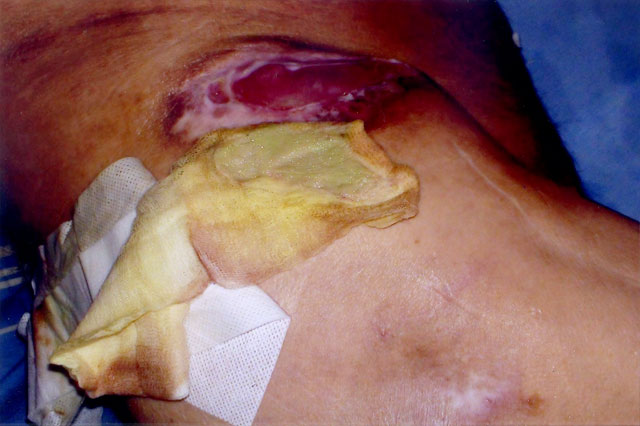

ΕΛΛΑΔΑ – Ψυχική Υγεία 2013: Πριν από δύο μέρες, οκτώ εργαζόμενοι του Κρατικού Θεραπευτηρίου Λέρου, κατέθεσαν έγγραφο με αρ.πρωτ.5868//22-5-2013 προς τον Διοικητή του Νοσοκομείου, καταγγέλλοντας ότι υπάρχει ασθενής σε δομή «προκάτ», με σοβαρότατο πρόβλημα υγείας, ο οποίος είναι χρόνια κλινήρης με κατακλίσεις αριστερού και δεξιού ισχίου [ΦΩΤΟ], ενώ προ διμήνου ανιχνεύθηκε βακτήριο με την ονομασία «ψευδομονάδα αερόβια», για το οποίο, όπως καταγγέλλουν οι εργαζόμενοι, δεν δόθηκε κανένα σχήμα φαρμακευτικής αγωγής.

Επίσης όπως θα διαβάσετε στο έγγραφο που ακολουθεί, η νοσηλευτική φροντίδα των κατακλίσεων του ασθενούς [ΦΩΤΟ], είχε και έχει ανατεθεί σε εργαζομένους με ειδικότητες αλλότριες προς τα νοσηλευτικά καθήκοντα (Δ.Ε. φύλακες ασθενών, Υ.Ε. βοηθοί θαλάμου, επιμελητές ασθενών και καθαριστές) και μάλιστα σε χώρο μη κατάλληλο για την αντιμετώπιση του συγκεκριμένου περιστατικού.

«Στην δομή προκάτ «ΙΡΙΣ» στην οποία υπηρετούμε προσφέρουμε της υπηρεσίες σε δώδεκα (12) ψυχικά ασθενείς. Ένας εκ των ασθενών μας είναι χρόνια κλινήρης, με κατακλίσεις αριστερού και δεξιού ισχίου. Προ διμήνου κατόπιν χειρουργικής επέμβασης και νοσηλείας του ανωτέρω ασθενούς στην χειρουργική κλινική του Νοσοκομείου ανιχνεύτηκε ψευδομονάδα αερόβια (δεν δόθηκε κανένα σχήμα φαρμακευτικής αγωγής για την καταπολέμηση της λοίμωξης).

Η νοσηλευτική φροντίδα των κατακλίσεων του ασθενούς είχε και έχει ανατεθεί σε εργαζομένους με ειδικότητες αλλότριες προς τα νοσηλευτικά καθήκοντα (Δ.Ε. φύλακες ασθενών, Υ.Ε. βοηθοί θαλάμου, επιμελητές ασθενών και καθαριστές) και μάλιστα στον χώρο της Δομής.